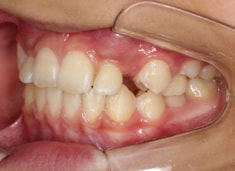

FX(フェイシャルアキシス)は85度なので東洋人の平均値に近く、下顎が前方に過剰成長するリスクは強くはありません。

しかしやはり上顎は劣成長で、下顎が優位な状態ではあります。

上下顎のギャップはありますが、顔面自体の幅径は良好な値を示していますので、スペース不足は拡大することによって解決できポテンシャルはあると考えられます。

左右の非対称もさほど強くありません。

骨年齢は実年齢よりも低めなので、今後下顎の旺盛な成長が見込まれます。